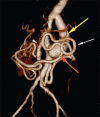

Dacron graft aneurysm with dissection

Dacron grafts have been used as a conduit for large caliber arteries for many years successfully. However, these grafts can undergo complications such as aneurysm formation, rupture, and failure. Evaluation of these complications are of paramount importance because of its tendency to rupture and cause death. Imaging plays an important role in identifying and monitoring of these complications, and also provides a road map to the vascular surgeons for early intervention and revascularization.